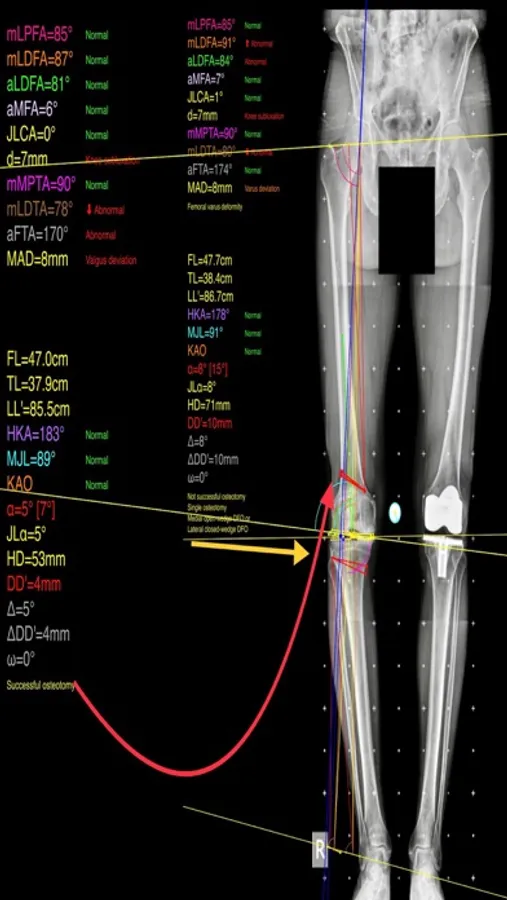

The app assists at preoperative correction planning by calculating :

-the amount of correction preoperatively by calculating the dimension of wedge size , the correction angle and osteotomy gap opening or closing.

-mechanical axis deviation (in mm) MAD, anatomical and mechanical femoral axes angle (aMFA),mechanical lateral proximal femoral angle (mLPFA), mechanical lateral distal femoral angle(mLDFA), joint line convergence angle (JLCA),mechanical medial proximal tibial angle (mMPTA), Mechanical lateral distal tibial angle (mLDTA), Hip Knee Ankle line (HKA) ,Mid joint line (MJL) orientation.

-objectively the deviation or deformity in the frontal plane (varus or valgus) and differentiate the level of deformity (femoral and or tibial origin) and according to measured angles objectively suggest where indicated, medial or lateral, open or closed-wedge distal femur osteotomy or high-tibial osteotomy or double osteotomies and avoiding unwanted obliquity of the joint line

-change the planned mechanical axis to pass at the preferred percentage (Fujisawa point) after evaluation of the residual cartilage thickness left on the involved compartment.

select the location of hinge point of correction osteotomy for planning of varus or valgus corrections

-evaluate in real time the success of intended osteotomy by evaluating the kinematic alignment of the knee (KAO), avoiding residual joint obliquity or malalignment.

-measure the correction angle adjusted due to ligament instability and preoperatively calculate the height of osteotomy gap opening.

-pressing + or - button, one degree of correction is added or subtracted respectively and the second plane of osteotomy emerges and printed in screen real offering real time simulation of the wedge osteotomy in an instant to comprehend in real time what parameters are affected and modify favourably the correction angle. All above mentioned angles and all limp axes are redrawn and updated accordingly for the given new correction angle. The drawn schematic gives the impression of settings act as a whole interchangable interacting unit.

-to combine correction- Biplanar-, at coronal plane and sagittal plane (based on Hernigou 2001 calculations ) on tibia slope and provide the direction of the plane (ω angle) in which the osteotomy (open or closed) should be made ,the height the opening or closing wedge and the correction angle (Δ angle),